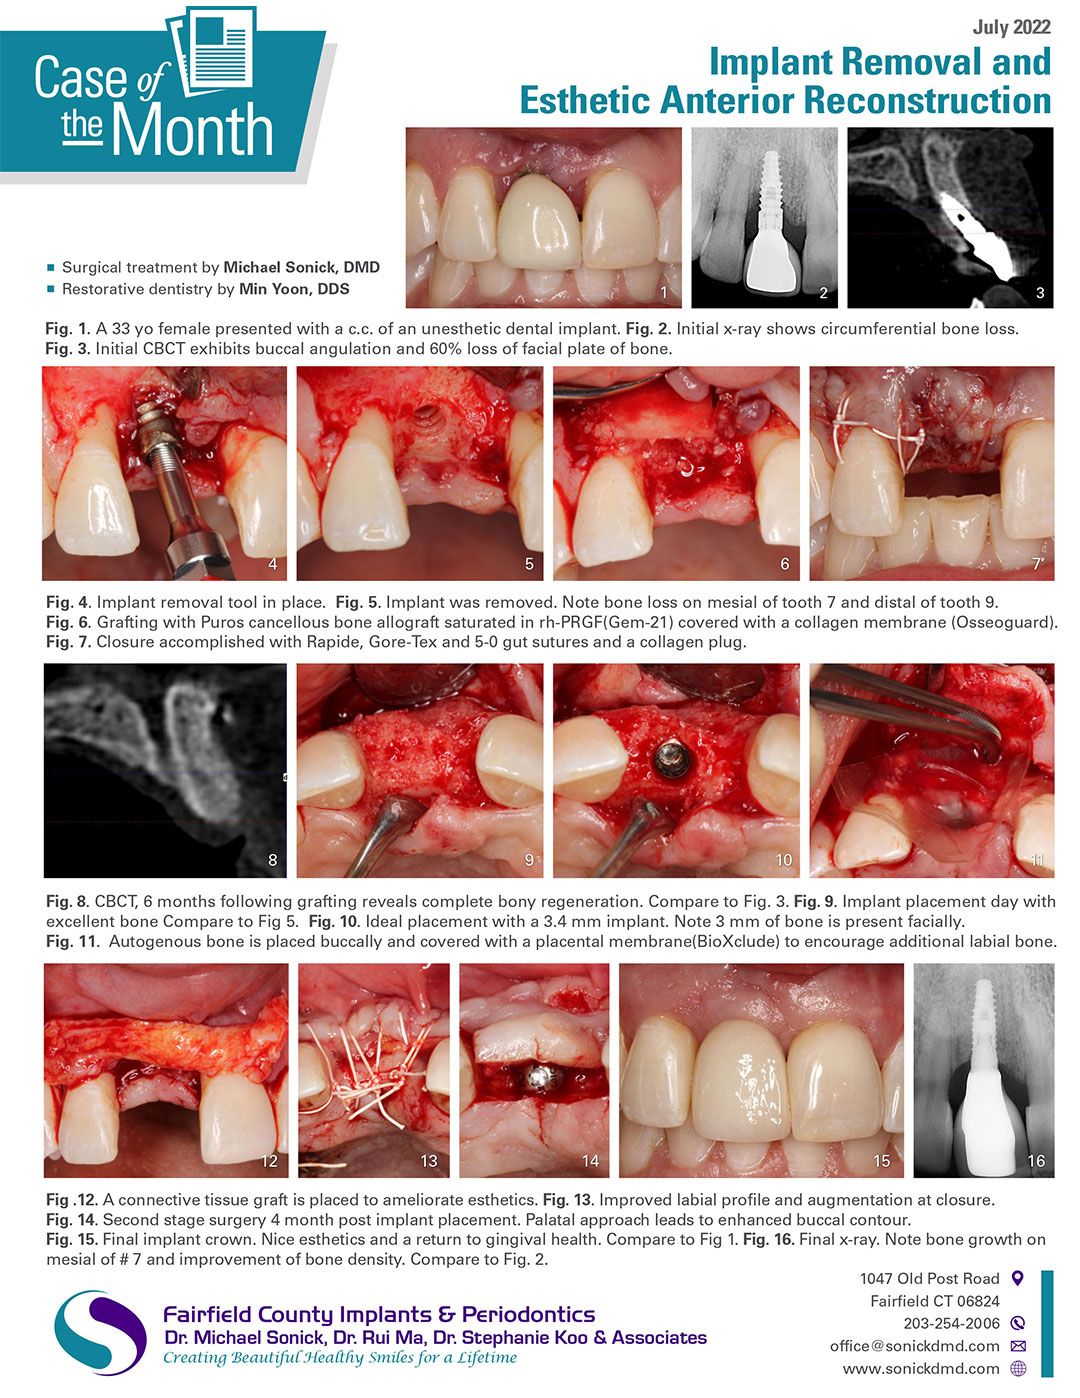

Case of the Month